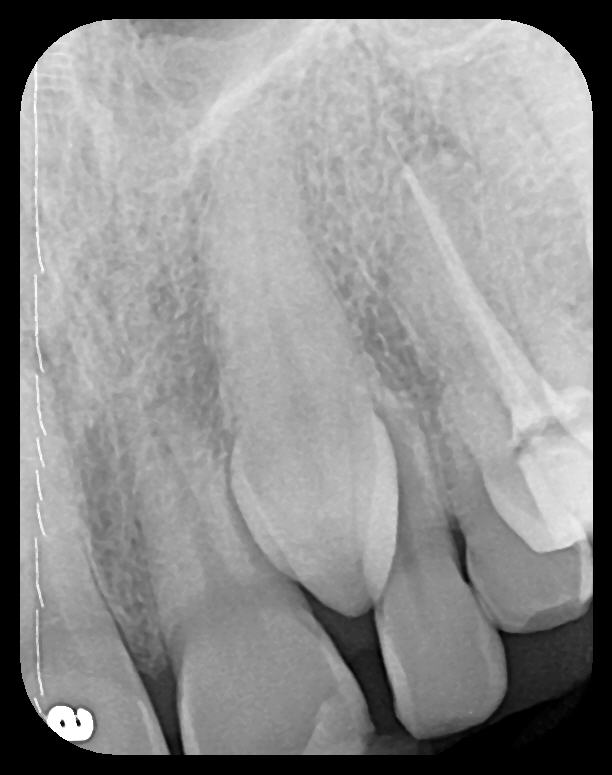

Fig 10.

A hemostat was used to obtain this PSP PA image of a potential fixed

prosthesis abutment, tooth No. 32. The hemostat is visible in the upper

left corner of the image. Hemostat stabilization of an HW sensor is

not possible and can damage the sensor if attempted.

Figure 10